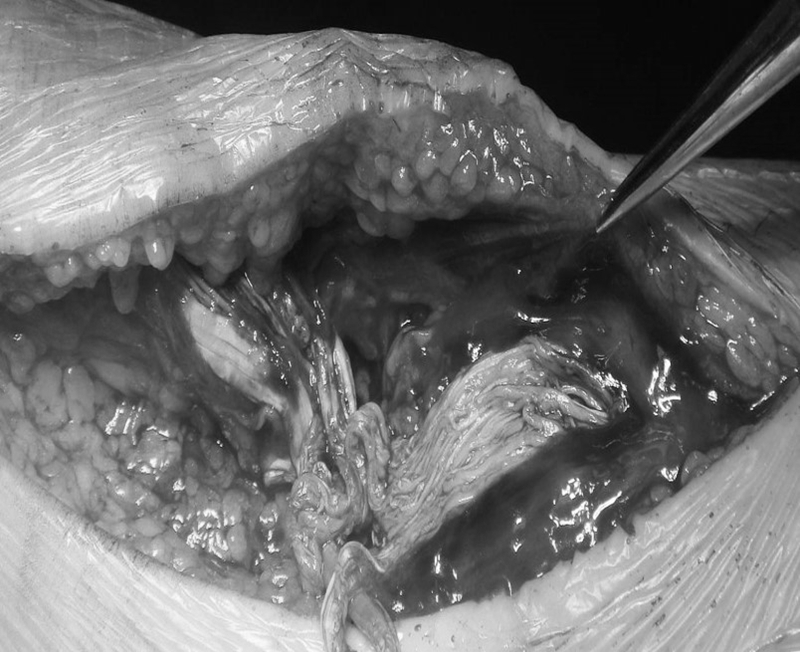

开放手术切口的选择:选择后内侧纵切口,而不推荐后正中切口,后正中切口会伴发鞋子磨损问题以及切口瘢痕破溃问题,有效避开腓肠外侧皮神经和小隐静脉。

常用缝合方法:Bunnell缝合法,改良Kessler缝合法,Krakow锁边缝合法。

Bunnell和改良Kellser法常用,具有强度好、软组织并发症少的优点,改良Krakow法强度更高,适合马尾状撕裂,线结多。

选择跟腱内侧纵切口;

应锐性切开至深筋膜(腱外膜),避免钝性剥离造成的皮下营养血管网破坏和脂肪液化,从而减少切口皮肤坏死、感染和和粘连;

保护腱周组织,避免破坏其从腹侧进入跟腱的血管束;

修复后跟腱应有足够强度且张力不可过大,以免阻断断端血供,影响愈合;术后石膏托固定于屈膝、跖屈位减轻吻合处张力;

线结包埋于断端,腱外膜间断缝合使线结位于皮下组织中,可减少线结刺激。皮肤缝合不建议连续皮内缝合。